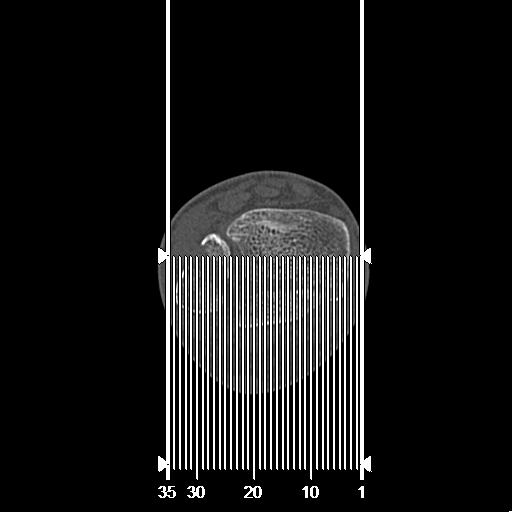

102803 1/12(キウスなし) 1/27 左下腿 4R 30歳女性 左脛骨軸内釘